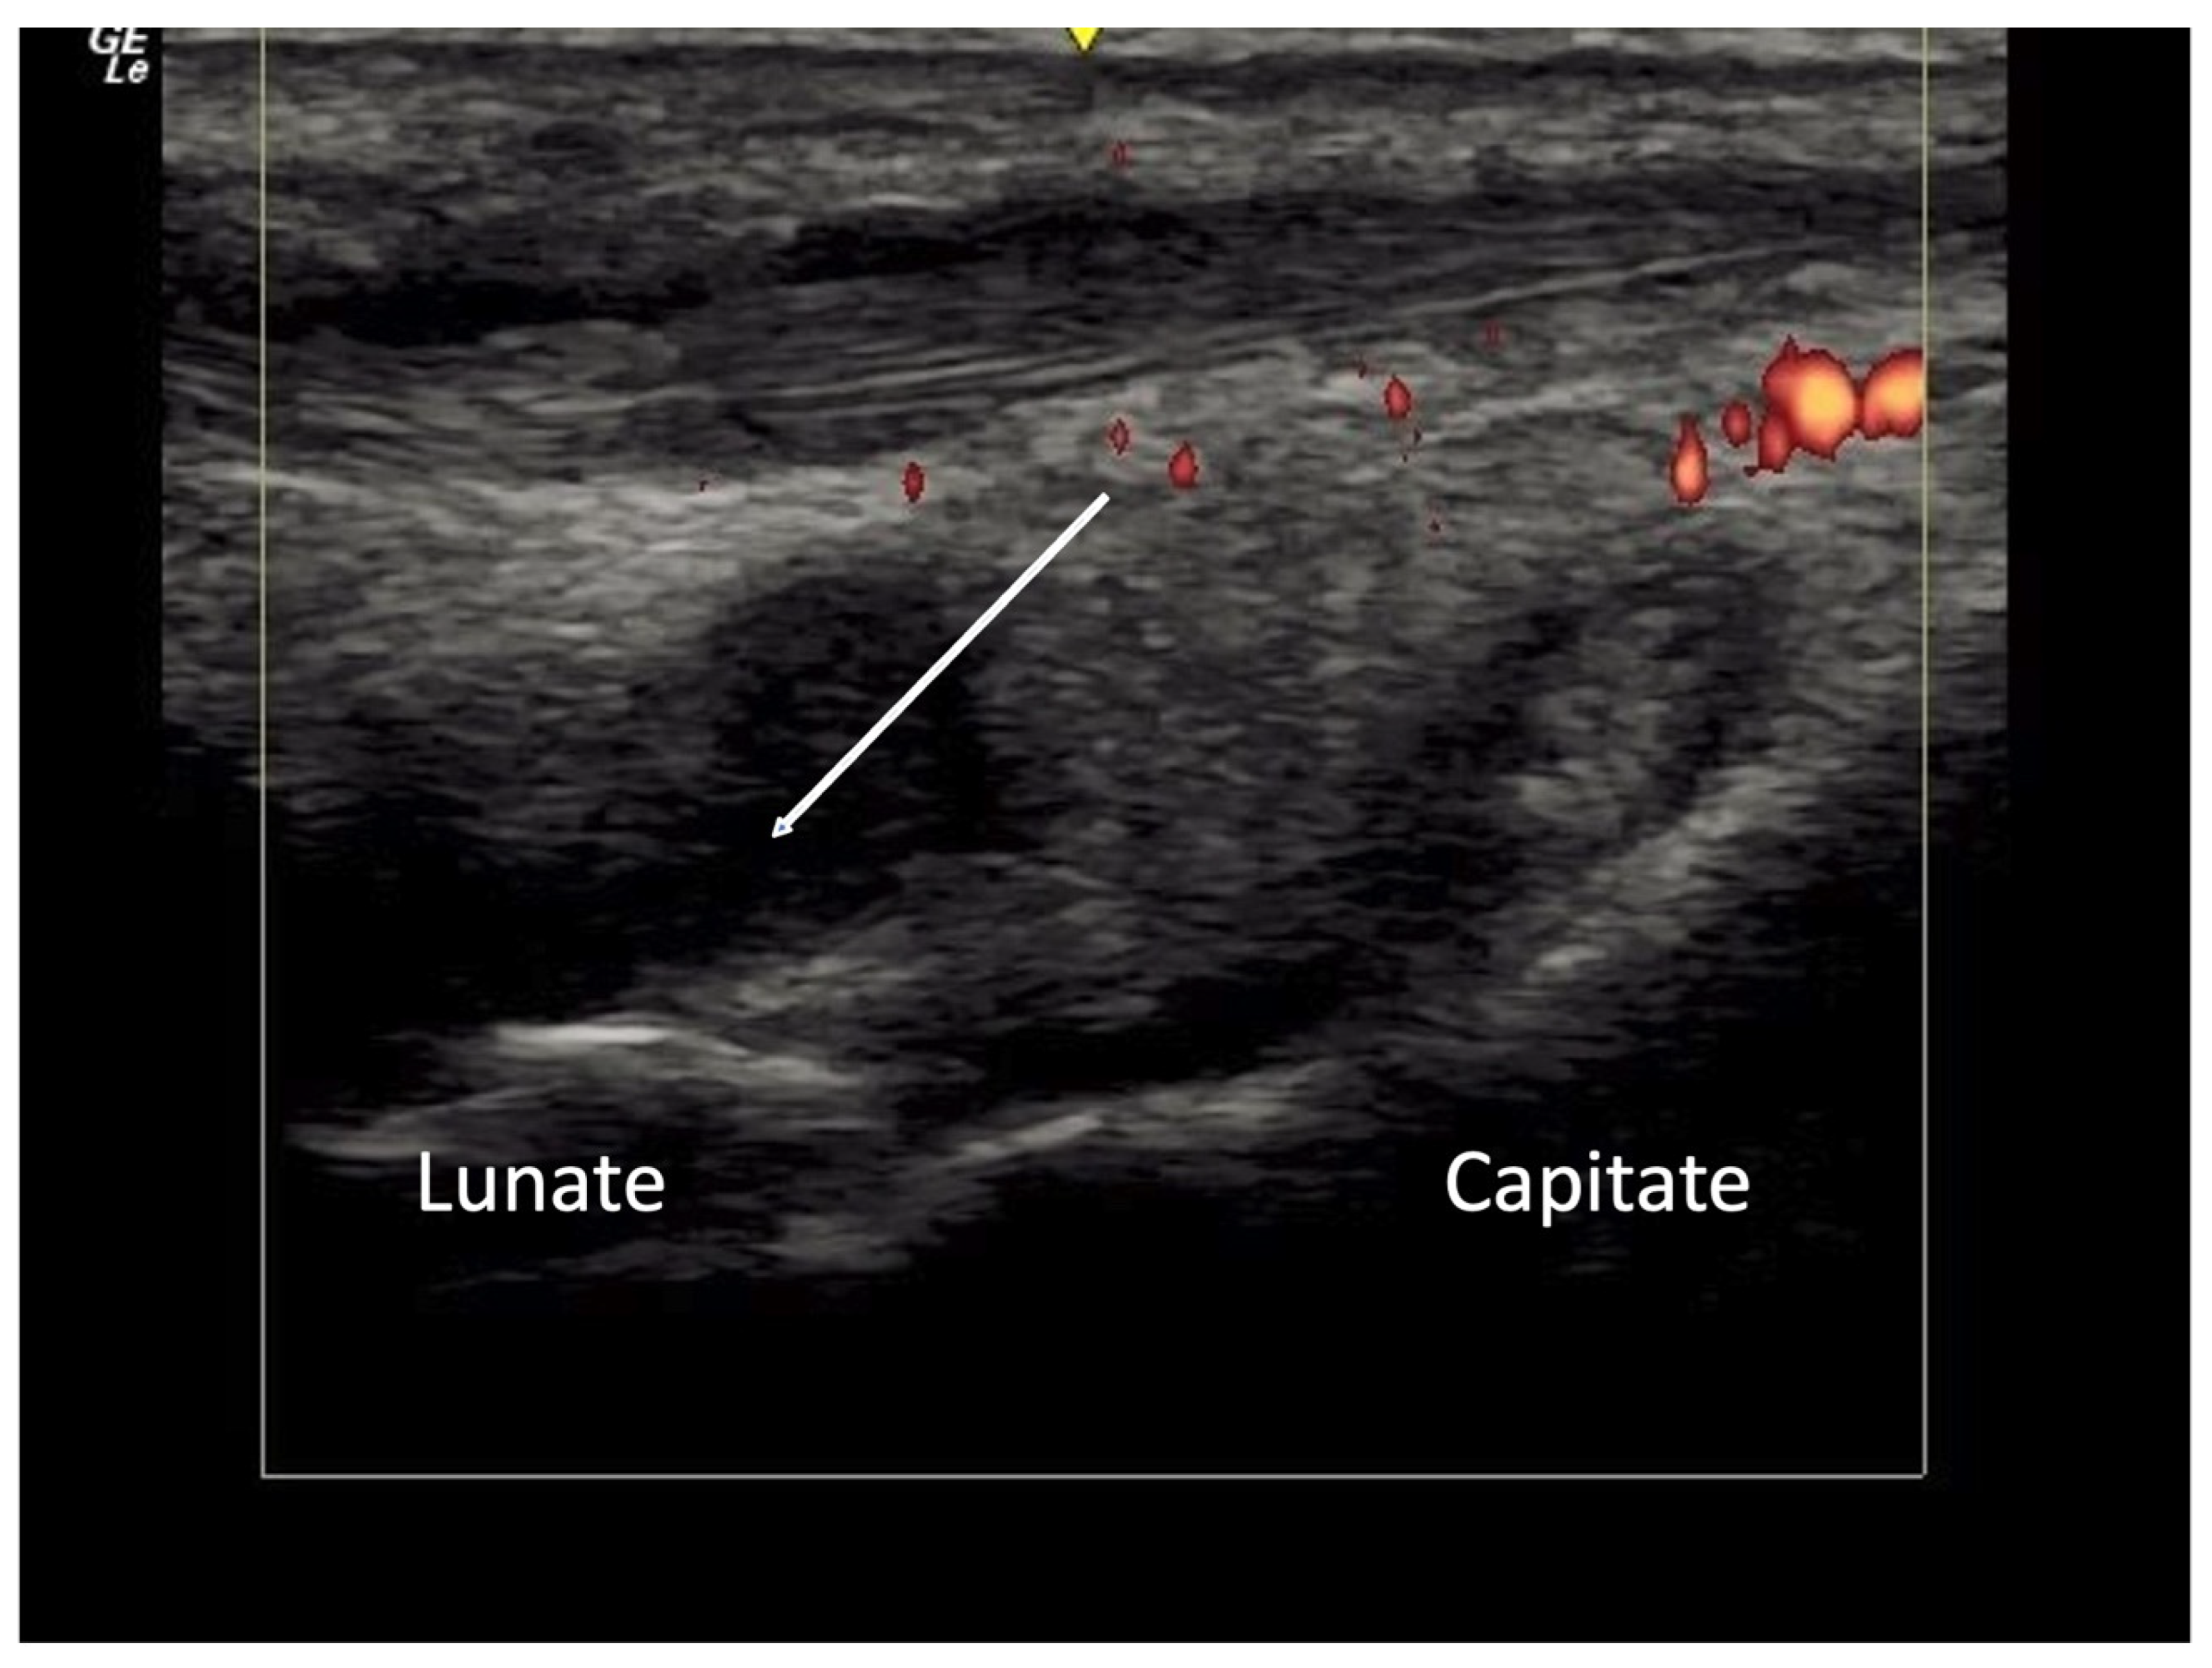

2.1. Joint Pathology

2.1.2. Inflammatory Arthritis

2.4. Vascular Pathology